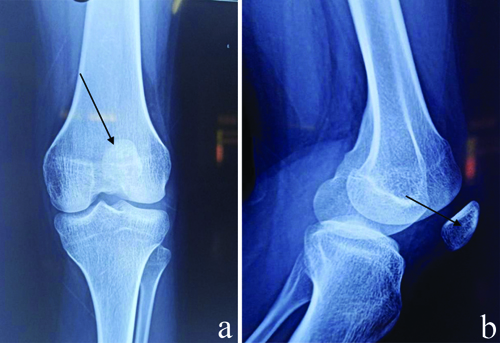

Deformed nails of upper limbs.

She was thereafter referred to the Medicine Department for her nail deformities and gastric complaints. All routine investigations including haemoglobin were normal. The patient was given a provisional diagnosis of irritable bowel syndrome with a high suspicion of NPS and was referred for an orthopaedic and ophthalmology opinion. The orthopaedic evaluation revealed swan neck deformity in her fingers [Table/Fig-4]. On radiological evaluation, she was confirmed to have left radial head subluxation [Table/Fig-5] and hypoplastic patella [Table/Fig-6a,b]. Ophthalmology evaluation revealed right eye glaucoma. The management plan for this patient was regular follow-ups every month to monitor her depressive symptoms and a close watch on the progression of her ocular disease or development of any renal disease. The patient was followed-up for eight months after discharge with gradual tapering of medications upon significant improvement in her depressive features and no progression of ocular disease.

a) Digital X-ray of left knee showing hypoplastic patella (arrow). b) Left knee showing hypoplastic patella.

In comparison to other fingers, the thumbnails are more severely affected, and nail irregularities worsen until they reach the little finger. In the case reported here, based on the history of loss of appetite, her nail deformities were initially thought to be koilonychia. Distal inter-phalangeal joints and reduced skin creases were common over the affected fingers. The patella is frequently involved and often appears hypoplastic or absent. On rare occasions, the patella may become dislocated or displaced, leading to painful, unstable, and limited knee extension. The radial head may subluxate due to lateral epicondyle hypoplasia and radial head dysplasia, which manifests as elbow asymmetry.